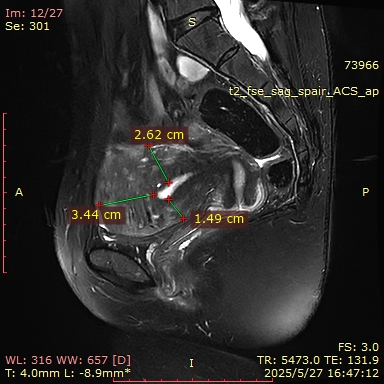

2025-05-26于深圳大学总医院查B超示:子宫前位,宫体形态饱满,大小约85mm*70mm*64mm,肌层回声增粗、不均匀,以宫底及后壁为著;后壁可见低回声区,范围约59mm*33mm,边界不清,内部回声欠均匀。内膜厚约6mm(双层),宫腔内未见明显异常回声。CDF1:宫内未见明显异常血流信号。

MRI(2025-05-27):子宫肌层增厚,其内信号欠均匀,肌层内见一等类圆形T2WI低信号,其内可见T1WI高信号,大小约为40mm*39mm。左侧附件区可见类圆形短T2异常信号影,大小约为8mm*5mm;右侧附件形态、大小、信号未见明显异常。盆腔少量积液。